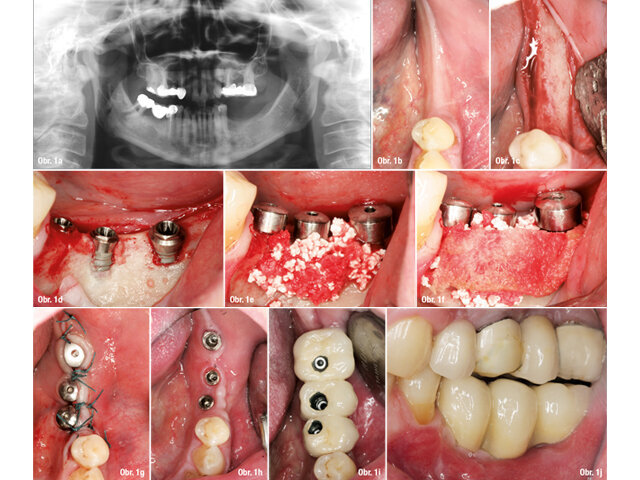

Pacient s dehiscencí ošetřený pomocí GBR s nezanořeným postupem: a) Předoperační panoramatický rentgenový snímek, b) Předoperační pohled na okluzi, c) Atrofie kosti alveolárního hřebene vizualizovaná po odklopení laloku, d) Zavedení implantátů do oblasti 35, 36 a 37, e) Syntetická kost překrývající dehiscenci, f) Resorbovatelná membrána aplikovaná přes kostní náhradu, g) Sutury, h) Zhojené měkké tkáně, i) Okluzální pohled na umístěnou protetickou práci, j) Laterální pohled na protetickou práci